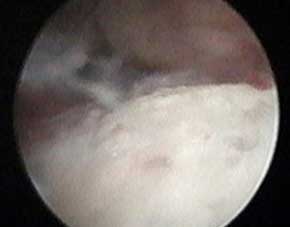

医生讲解:针刀镜技术可直观鉴别诊断风湿病

针刀镜技术利用其独有的高清内窥镜,在手术过程中可全面直观鉴别诊断相关病情,根据关节滑膜的充血和水肿、关节软骨损伤程度等病理改变可协助鉴别类风湿、痛风等疾病。还可用于关节及软组织结构急慢损伤的观察诊断,提取各病变组织的活检标本,避免二次检查伤害。

- 膝类风湿检查

针刀镜技术内窥镜下,类风湿患者膝关节炎症严重,滑膜增生